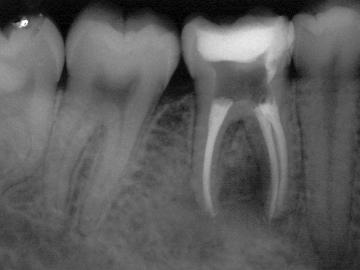

Każdy ząb zbudowany jest z zębiny i szkliwa, czyli substancji tworzących rdzeń zęba oraz miazgi, która odżywia i unerwia ząb. Niestety drobnoustroje bytujące w ubytkach zębów prowadzą do nieodwracalnych stanów zapalnych miazgi zęba, które skutkują koniecznością leczenia kanałowego. Generalnie zabieg polega na usunięcia zainfekowanej miazgi, poszerzenia światła kanałów i ich dokładnego wypełnienia. Dzięki tej popularnej metodzie możemy zachować zęba w jamie ustnej na dalsze lata. Jednak ze względu na brak odżywania, zęby leczone kanałowo są kruche i podatne na złamania. W związku z tym wymagają odpowiedniego zabezpieczenia aby służyły przez kolejne lata. Najpopularniejszą metodą to pokrycie zęba kosmetyczą koroną porcelanową.